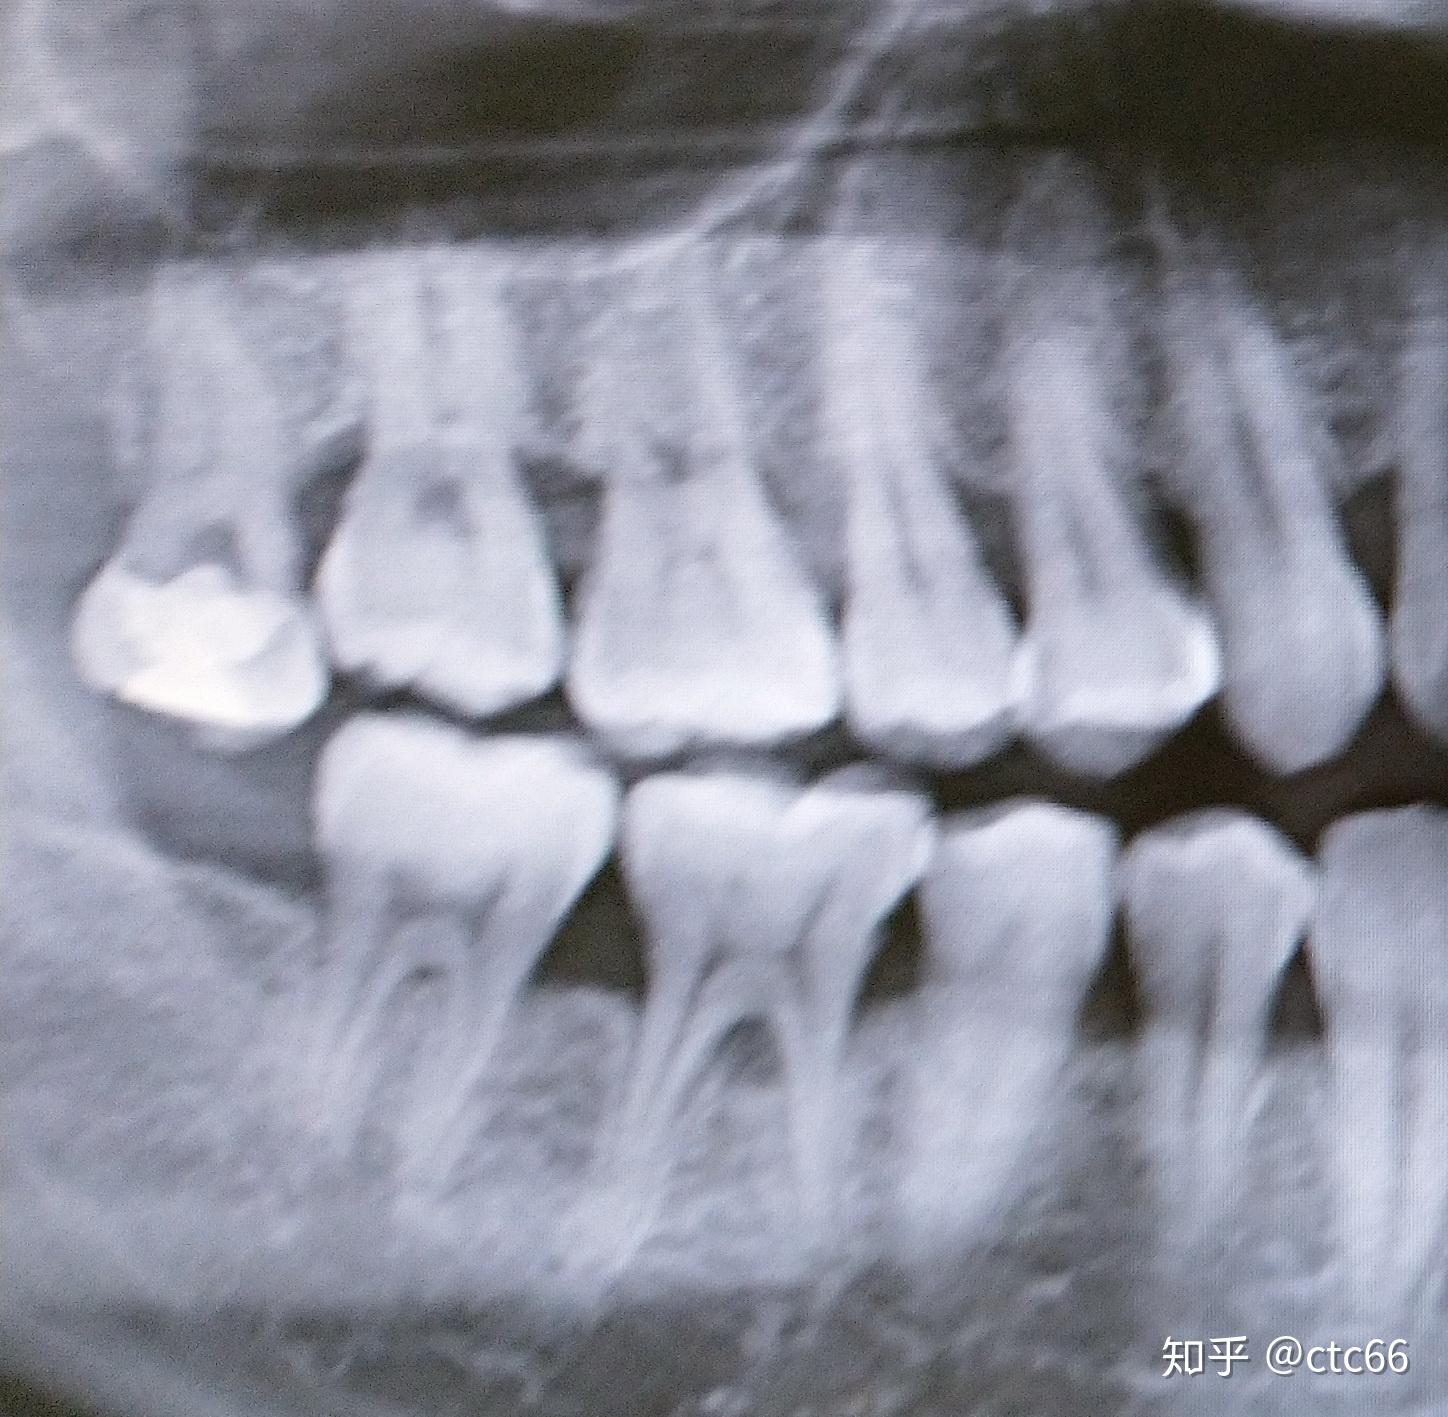

上下都是阻生智齿,求问高手医生,该如何拔除?

图片尺寸3264x2448